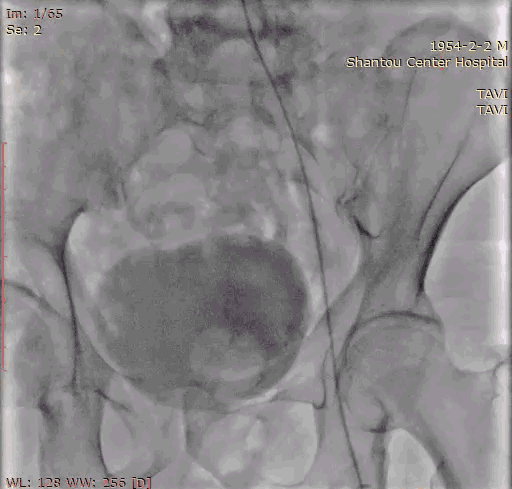

入路:入路观察是否有溃疡、钙化、迂曲、血管狭窄等情况,以判断夹层风险。该病人入路情况良好,优先选择右股作为输送系统主入路。

心尖薄,导丝塑性需注意形态,入路可,右股做为主入路。

入路直径足够,分叉点足够高。右股作为主入路。